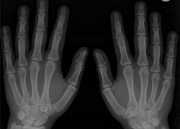

Osteoartritis, koji nastaje trošenjem i razaranjem zglobne hrskavice, kod mnogih se ljudi uglavnom pojavljuje nakon četrdesete godine, a da je došlo do određenih promena u kolenom zglobu, često nas upozore tek bolovi. U poslednjih desetak godina primečen je povećan broj mladih sa artritisom. Bolovi se prvo javljaju samo na početku fizičke aktivnosti kao početni, inicijalni bolovi, odnosno kod izlaganja većim opterećenjima.